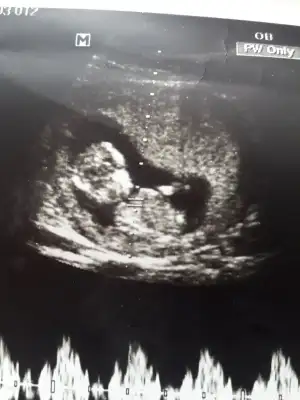

Merhaba ben de bir tahmin alabilir miyim. 11+4 haftalıkken.